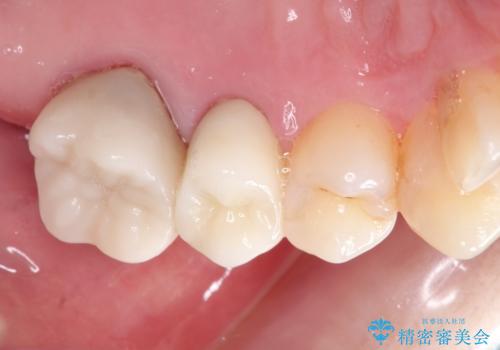

金属のかぶせ物をセラミックへ 根管治療からの再治療

根管治療からの再治療を行ったことにより、治療期間が多少長くなりましたが、今後再治療の必要性があまりないような、精度の高い治療ができました。